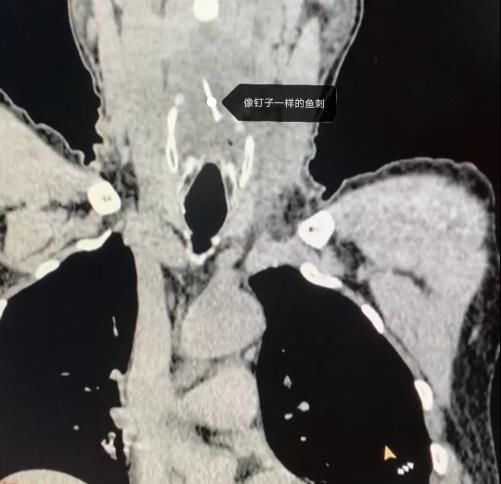

近日,家住饶河的王先生在家吃“嘎牙子”鱼时,不小心被鱼刺卡住了喉咙,但王先生并没有当回事,喝了几口醋,吞了馒头想把刺“推”下去,结果却不如人意,喉咙越来越疼了。王先生又用了几天消炎药后仍是疼痛难忍,于是去了当地医院,做颈部CT检查,结果显示鱼刺完全没入软组织内。经多方打听,王先生来到哈医大四院就诊。

【 鱼刺卡喉|鱼刺卡喉用“老土方”?专家:不科学且危险!】经过详细检查,哈医大四院耳鼻咽喉头颈外科主任周彬为王先生进行急诊全麻下支撑喉镜下下咽后壁切开异物取出术。术中可见咽后壁粘膜光滑,会厌高度偏左侧的咽后壁略隆起。在隆起处以激光纵行切开粘膜及粘膜下组织,脓性液体流出,其内可见一白色鱼刺。完整取出鱼刺,可见其上端呈针尖状,整体呈弧形,边缘锐利光滑,无破损。术后,王先生恢复良好。